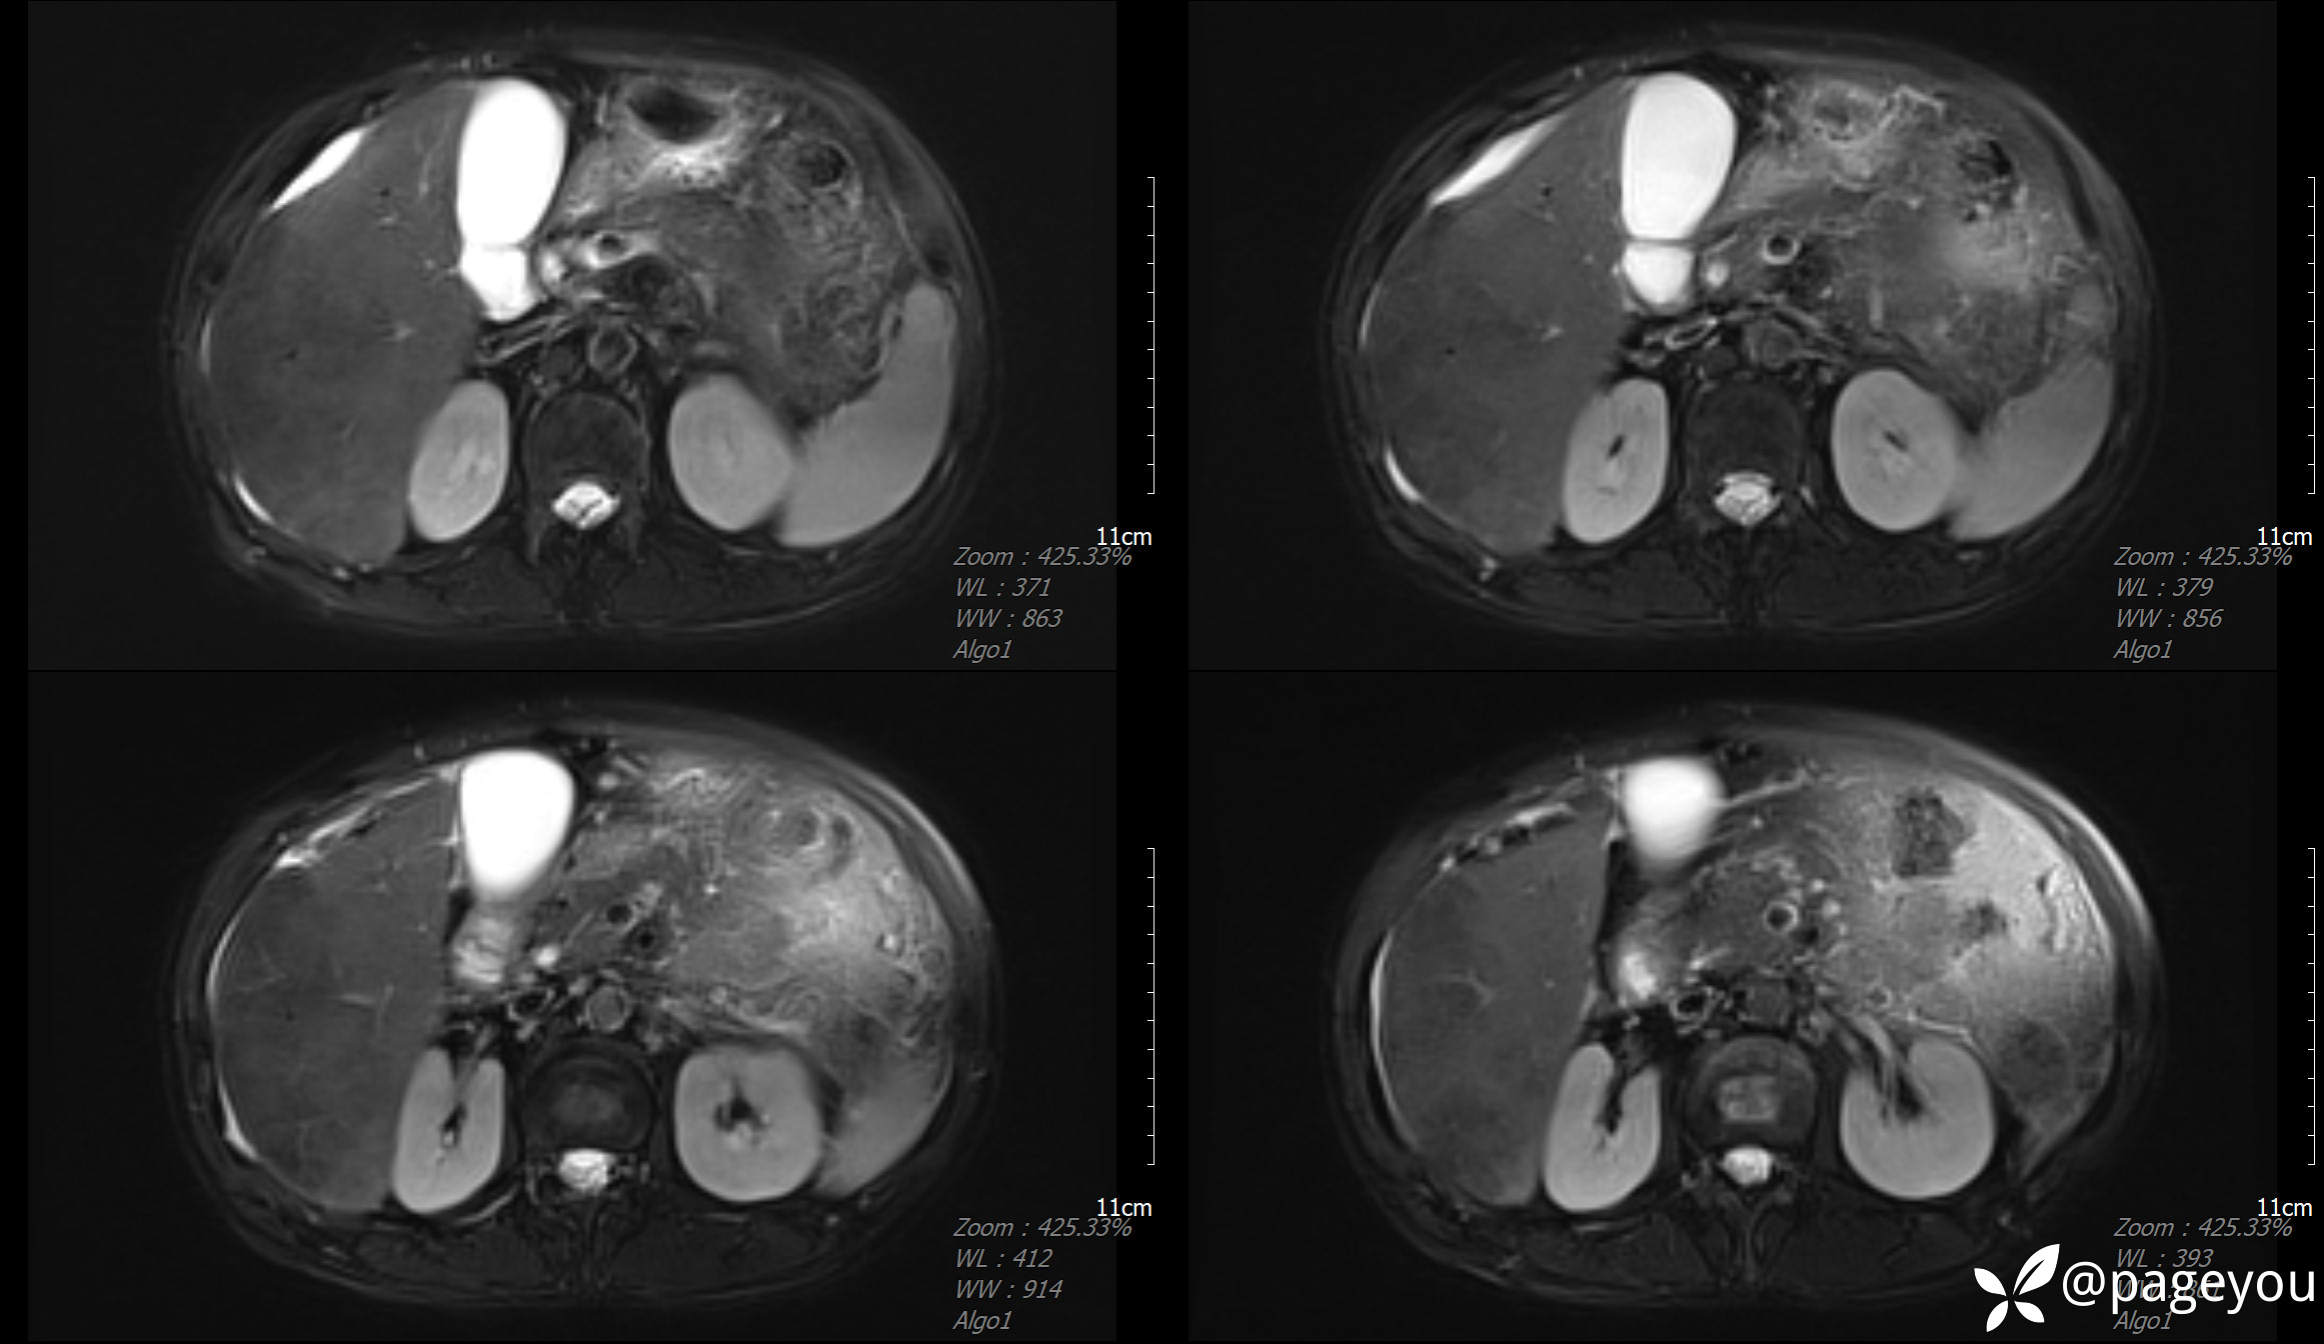

MRI检查: